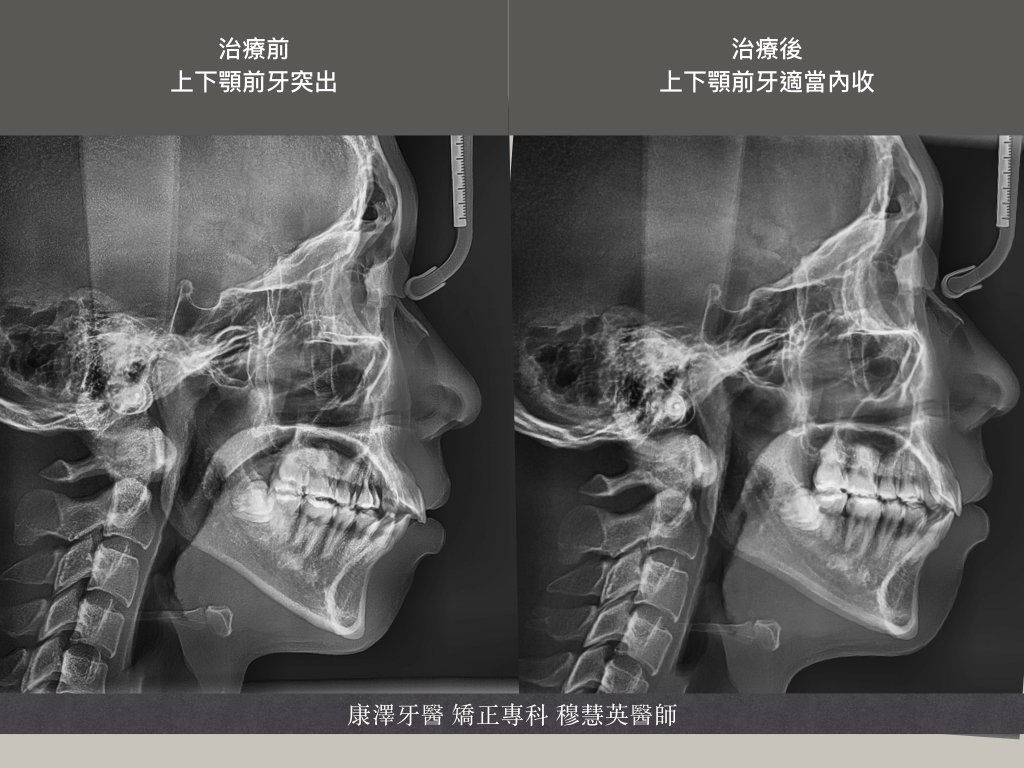

本病例為一名22歲男性,主要矯正訴求是改善外觀,尤其是上前牙輕微暴牙的情況。檢查結果顯示,患者的上前牙有輕度前突,且上顎牙弓呈V型,牙弓較窄。此外,前牙區域有明顯縫隙,這不僅影響美觀,亦對咬合功能造成了一定的困擾。

診斷與治療目標:根據臨床診斷,患者呈現輕度暴牙和窄牙弓。治療目標旨在改善前牙暴牙、關閉牙縫,並矯正牙弓形態,以達到理想的美觀和咬合效果。

治療結束後,患者的牙齒排列顯著改善。上顎的V型牙弓問題已得到矯正,前牙區域的縫隙也完全關閉,輕微暴牙問題有了顯著改善,整體外觀更加和諧自然。此外,患者反映治療後咬合穩定,咀嚼功能明顯提升。

總結:此病例展示了通過不拔牙的傳統矯正方式,有效改善輕微暴牙、窄牙弓及牙縫問題。在治療過程中,牙弓重塑與縫隙關閉,不僅成功改善了患者的外觀,還調整了咬合關係。這一案例為類似患者提供了有價值的治療參考,並證明了輕微暴牙的患者可以通過不拔牙矯正達到理想效果。